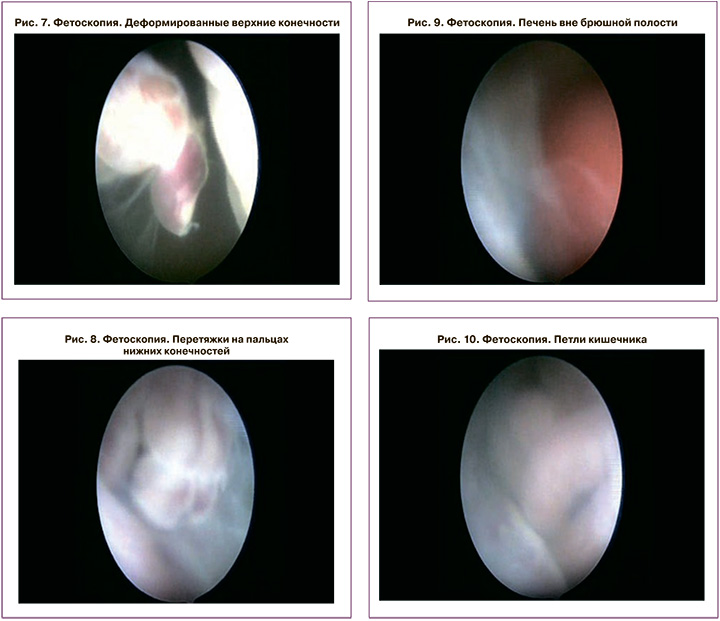

Учитывая абсолютно неблагоприятный прогноз, пациентка была направлена в стационар дневного пребывания научно-поликлинического отделения Центра для прерывания беременности. Перед выполнением процедуры прерывания беременности с целью подтверждения и дополнительной оценки аномалий развития плода была произведена трансцервикальная фетоскопия (рис. 6–10). Использовался фетоскоп с углом обзора 30°, диаметром 2,7 мм производства фирмы Karl Storz, Германия. Для определения хромосомных аномалий плода было выполнено кариотипирование.

Во время фетоскопии дополнительно в полости матки были выявлены множественные амниотические тяжи, не диагностированные при ультразвуковом исследовании (рис. 6). При генетическом исследовании плода получен нормальный кариотип – 46 ХХ.

Во время детальной оценки анатомического строения внутренних органов плода при помощи двухмерной и трехмерной эхографии были выявлены: дефект передней брюшной стенки и эвентрация органов брюшной полости – печень и петли кишечника располагались вне брюшной полости (рис. 1, 4, 5). При сканировании скелета плода обращала на себя внимание деформация позвоночника в поясничном и грудном отделах (рис. 2). При исследовании конечностей плода диагностировалось отсутствие всех пальцев правой верхней конечности и двух пальцев левой (рис. 3, 5).